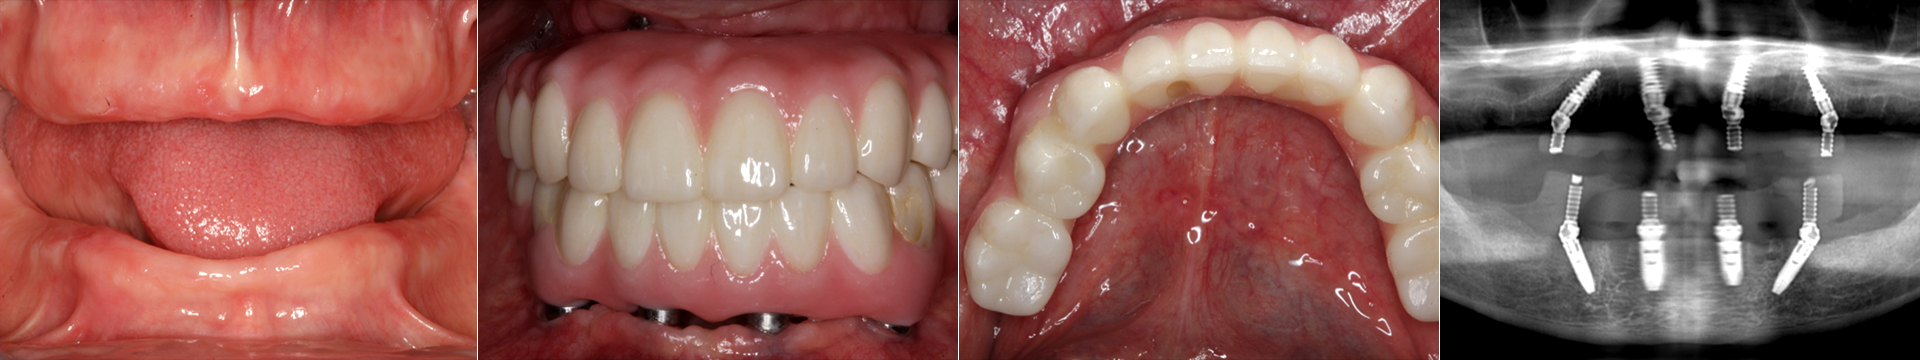

edentulous_case_quartet